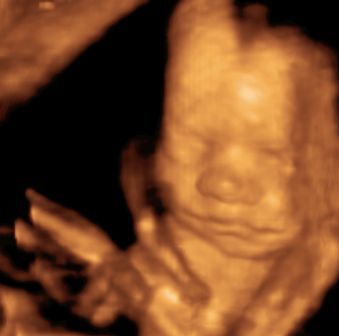

Na, és rakok fel pár képet: Btw: Tiszta apja! :)

Kép Megtalálta az ujját... Kép Cumizik :) Kép Nagyon cumizik :) Bal kezes lesz úgy tűnik. :) Kép Kép Turcsi nózi :)